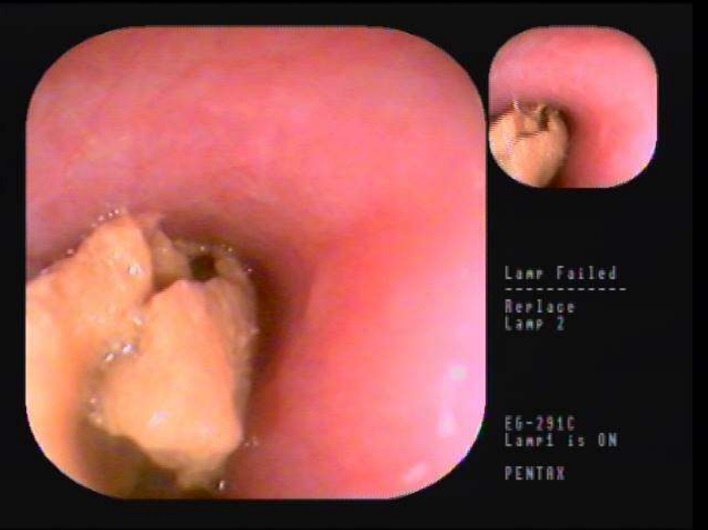

| Kết quả nội soi dị vật. Ảnh: BVCC |

Sau khi nhập viện, ê-kíp bác sĩ sau khi thăm khám và thực hiện cận lâm sàng đã xác định phần thức ăn bị vướng tại 1/3 dưới thực quản của người bệnh.

Bác sĩ Đức cho biết: “Đây là một trường hợp đặc biệt bởi phần dị vật là khối thức ăn khá lớn đã bị vỡ nát và gây khó khăn khi thực hiện thủ thuật này. Các bác sĩ phải chia dị vật ra thành nhiều phần nhỏ sau hơn 45 phút, ê-kíp đã gắp hoàn toàn phần thức ăn ra khỏi thực quản cho người bệnh”.